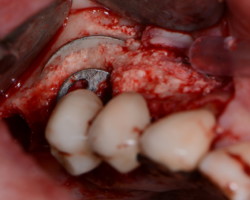

- Phase correctrice : créer des conditions compatibles avec la maintenance. (chirurgie résectrice, implantoplastie, correction prothétique)

- Phase réparatrice: Réduire la profondeur de poche et réparer les tissus détruits.

Techniques résectrices

Techniques régénératrices

Techniques combinées